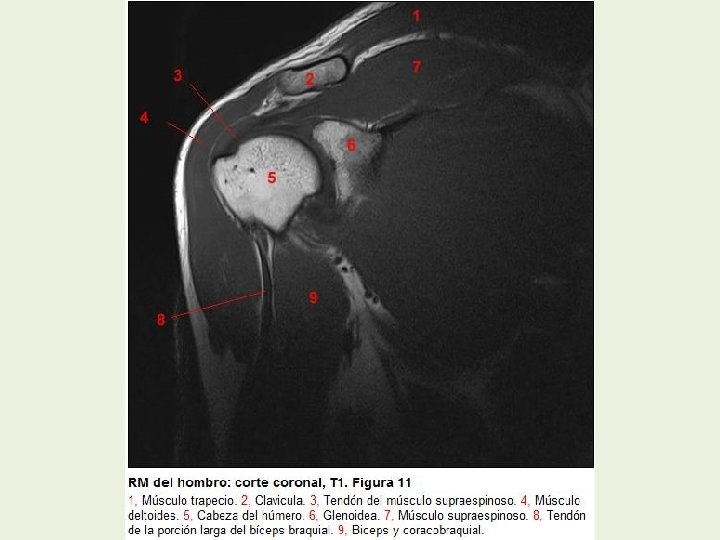

Hombro Cortes coronales RMN